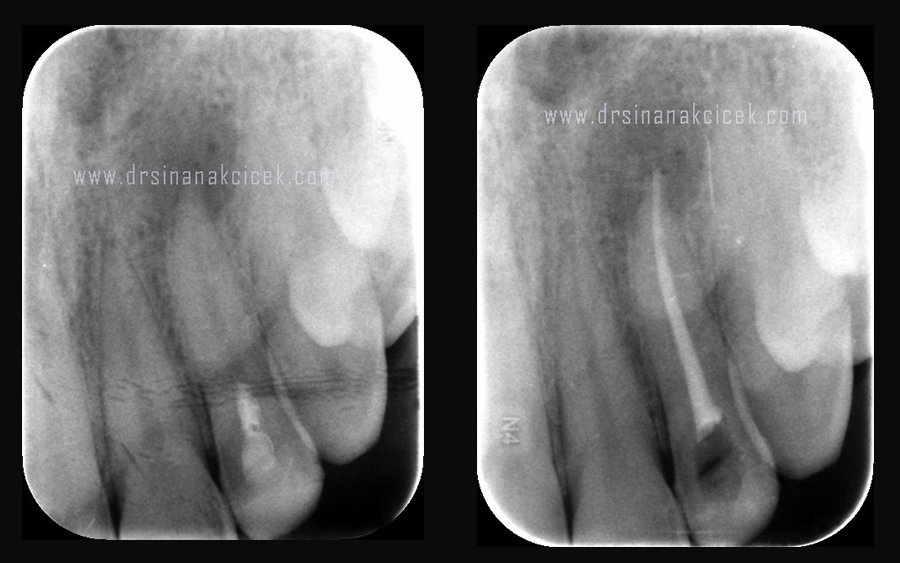

Kanal tedavisi yapılmış bir dişte problem varlığında tedavinin yenilenmesi işlemi retreatment olarak adlandırılmaktadır. Kanal tedavisinin ana prensibi kök kanal sisteminin tamamen mikroorganizmalardan arındırılması üzerine kuruludur. Mikroorganizmalardan arındırılmış bir kök kanal sistemi tekrarlayan enfeksiyonları önleyebilmek için üç boyutlu olarak tamamen doldurulmalıdır.

Kök içerisinde doldurulmadan bırakılmış alanlar ileride sorun teşkil edebilirler. Bu nedenle yetersiz doldurulmuş kök kanalları herhangi bir semptom yoksa 6 ayda bir mutlaka bir endodontist tarafından değerlendirilmeli, eğer semptom varsa hemen yenilenmelidir. Kanal tedavisi yenilenmesi ile büyük oranda başarı elde edilebilmekte olsa da bazı durumlarda tek başına yeterli olamadığı durumlarda belirli dişlerimiz için kök ucu rezeksiyonu seçeneği sayesinde başarı elde edilebilmektedir.

Kanal tedavisinin yenilenmesi daha önceden yapılan kanal tedavisi gibi yapılır, Yenilenme işlemi aşamaları da kanal tedavisine benzerlik gösterir. Kanal tedavisinin yenilenmesi, İlk seansta kanallardaki kök kanal dolgu materyalleri çıkarılır. Yerine bakterileri yok etmek ve enfeksiyonu ortadan kaldırmak için özel ilaçlar yerleştirilip diş geçici dolgu malzemesi ile kapatılır. 7-10 gün sonra bu ilaçlar çıkarılıp kanallar temizlenip kanal dolgusu yapılır. İnatçı enfeksiyon varlığında bu işlem enfeksiyon tamamen ortadan kalkana kadar bir kaç kez tekrarlanır.